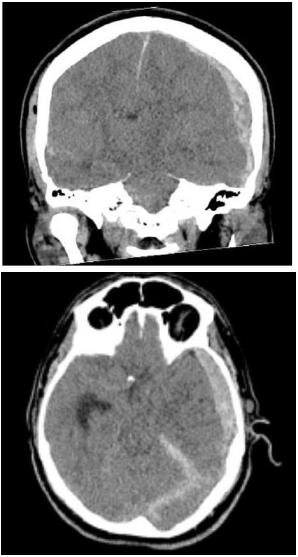

Paciente do sexo masculino, 23 anos, com quadro de traumatismo cranioencefálico após acidente automobilístico é levado para avaliação na emergência. Ao exame, apresentava Glasgow de 6. Foi realizada tomografia de crânio que mostrou o seguinte achado:

Enunciado 4576544-1

Quanto ao caso descrito e considerando o achado, é correto afirmar que